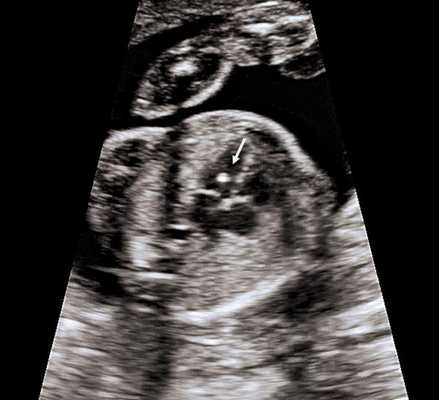

4. Гиперэхогенный фокус в желудочке сердца.

Это термин, говорящий о повышенной эхогенности (яркости) небольшого участка сердечной мышцы на ультразвуковом изображении. Выявление гиперэхогенного фокуса в сердце НЕ является пороком развития сердца, а просто отражает характер его ультразвукового изображения. Гиперэхогенный фокус возникает в месте повышенного отложения солей кальция на одной из мышц сердца, что не мешает нормальной работе сердца плода и не требует никакого лечения.

Почему у плода может выявляться гиперэхогенный фокус в сердце?

Иногда гиперэхогенный фокус в сердце выявляется у абсолютно нормальных плодов, и при УЗИ в динамике этот признак может исчезать. Наличие гиперэхогенного фокуса в сердце плода может быть проявлением хромосомных болезней плода, в частности, синдрома Дауна. В связи с этим при обнаружении гиперэхогенного фокуса проводится тщательная оценка анатомии плода. Однако этот маркер относится к «малым» маркерам синдрома Дауна, поэтому выявление только гиперэхогенного фокуса в сердце не повышает риск наличия синдрома Дауна и не является показанием к проведению других диагностических процедур.

Что делать при выявлении гиперэхогенного фокуса в сердце плода?

Если у плода выявлен ТОЛЬКО гиперэхогенный фокус в сердце, то никаких дополнительных обследований не требуется; риск болезни Дауна не увеличивается. На плановом УЗИ в 32-34 недели еще раз будет осмотрено сердце плода. В большинстве случаев гиперэхогенный фокус в сердце исчезает к этому сроку беременности, но даже если он продолжает оставаться в сердце, это никак не влияет на здоровье плода и тактику ведения беременности.